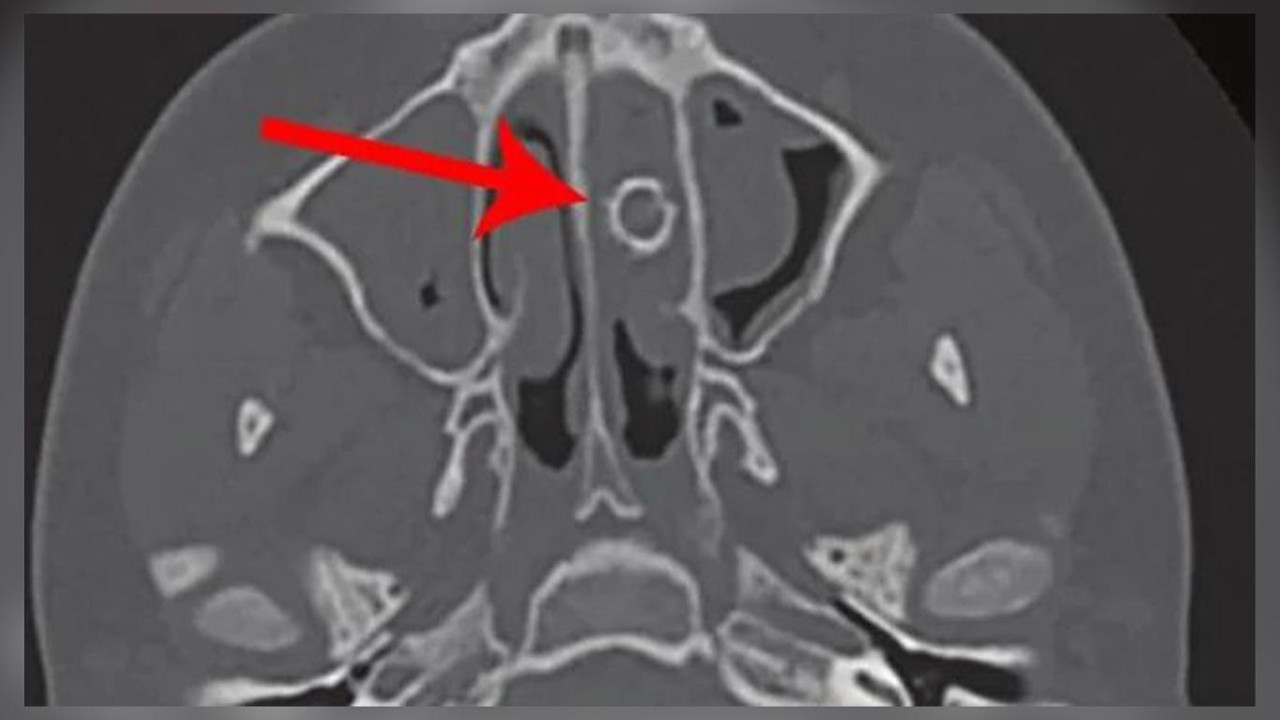

Kontrolden yaklaşık 1 yıl sonra doktora giden genç, sıkıntılarının devam ettiğini söyledi. Doktorlar daha sonra tomografi çekti ve burun boşluğunda 9 mm''lik dairesel bir cisim olduğunu fark etti. Genç, daha sonra havalı tüfek mermisi olduğu anlaşılan nesnenin çıkarılması için ameliyat oldu.